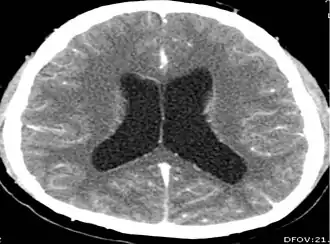

| Magnetic resonance image of a patient with neurocysticercosis demonstrating multiple cysticerci within the brain[1] | |

CT scans and magnetic resonance imaging (MRI) give objective information about the number and pattern of lesions, the stage of healing, and how the immune system is responding to the parasites.[19] MRIs are better for evaluating different spatial planes and provides clearer images, which helps in identifying small lesions at the back of the brain or near the skull that may be missed on CT scans. CT scans are more sensitive at detecting calcium buildup in the brain due to its ability detect calcifications in the brain.[30]

Live vesicular cysts are small, round lesions with little swelling around them and do not need contrast for imaging. The tapeworm head (scolex) usually appears as an asymmetric nodule inside the cysts. Multiple live cysts with these heads corroborate the diagnosis. Once the cysts begin to break down (colloid cysts), their borders become unclear, they are surrounded by swelling and exhibit significant ring or nodular contrast enhancement. Calcified cysticerci are shown on CT scans as non-enhancing hyperdense nodules without swelling.[20]